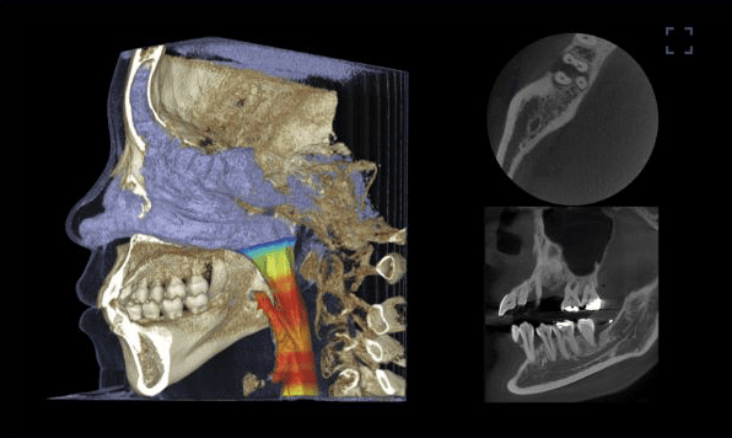

必要領域をコントロール。 世界初フリーFOV

LEDライトにより撮影範囲を自由に調整確認歯科市場では初めてMedical Chest x-ray Light Guideを搭載しました。

ライトガイドビームで誰でも簡単に領域を指定することができます。この機能で、部分撮影などを自在に微調整できます。 -

細部まで高解像度の診断が可能

正確な診断のため、広域撮影だけでなく、ニーズに合わせてスキャン量をライトガードで自由に調整できるため、細部まで高解像度の診断が可能です。

舌、気道など軟組織の評価にも活用されています。